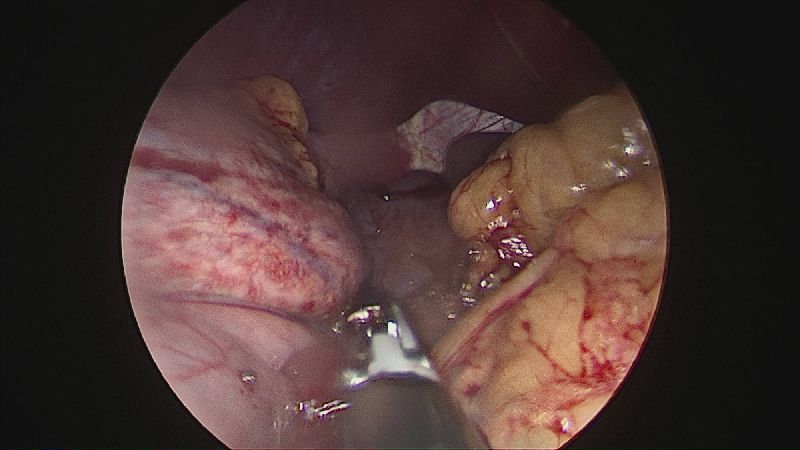

Gastrectomia longitudinală (gastric sleeve) este o intervenție care produce scăderea în greutate prin două mecanisme: restrictiv (îndepărtează o mare parte din stomac lăsând un rezervor de 80-120 ml) și hormonal (prin extirparea fundului gastric se reduce semnificativ secreția hormonului foamei, grelina).

Operația ”de micșorare a stomacului” se realizează miniminvaziv (laparoscopic) și constă în îndepărtarea marii curburi gastrice cu păstrarea antrului gastric și a micii curburi sub forma unui tub calibrat pe o sondă.

Tehnica aduce beneficiile chirurgiei laparoscopice, durere redusă, externare în primele 48 ore de la intervenție. Avantajul său constă în confortul oferit pacientului care prezintă senzația de sațietate rapid prin umplerea unui stomac de doar 100 ml, reducerea senzației de foame prin suprimarea secreției de grelina. De asemenea, nu modifică traseul alimentelor, nu exclude segmente digestive din circuit și pierderea excesului ponderal poate ajunge până la 100%.